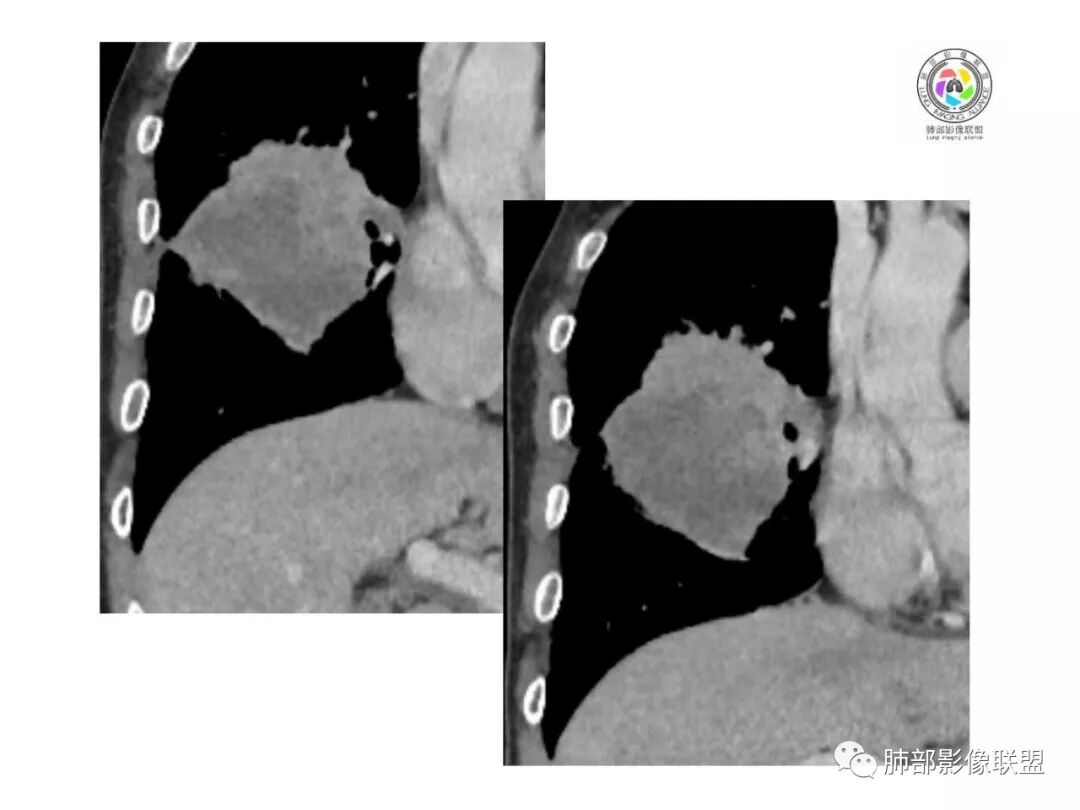

患者中老年男性,体检发现肺部占位。

胸CT:右肺中叶实性占位性病变,呈膨胀性生长,对斜裂明显挤压,右肺中叶外侧段阻塞,并在边缘可见分叶、毛刺、棘突样改变,胸膜牵拉;增强可见病灶明显强化,可见边缘模糊血管影,病灶内可见大片状低密度区,隆突下可见肿大淋巴结。

诊断考虑:恶性病变。